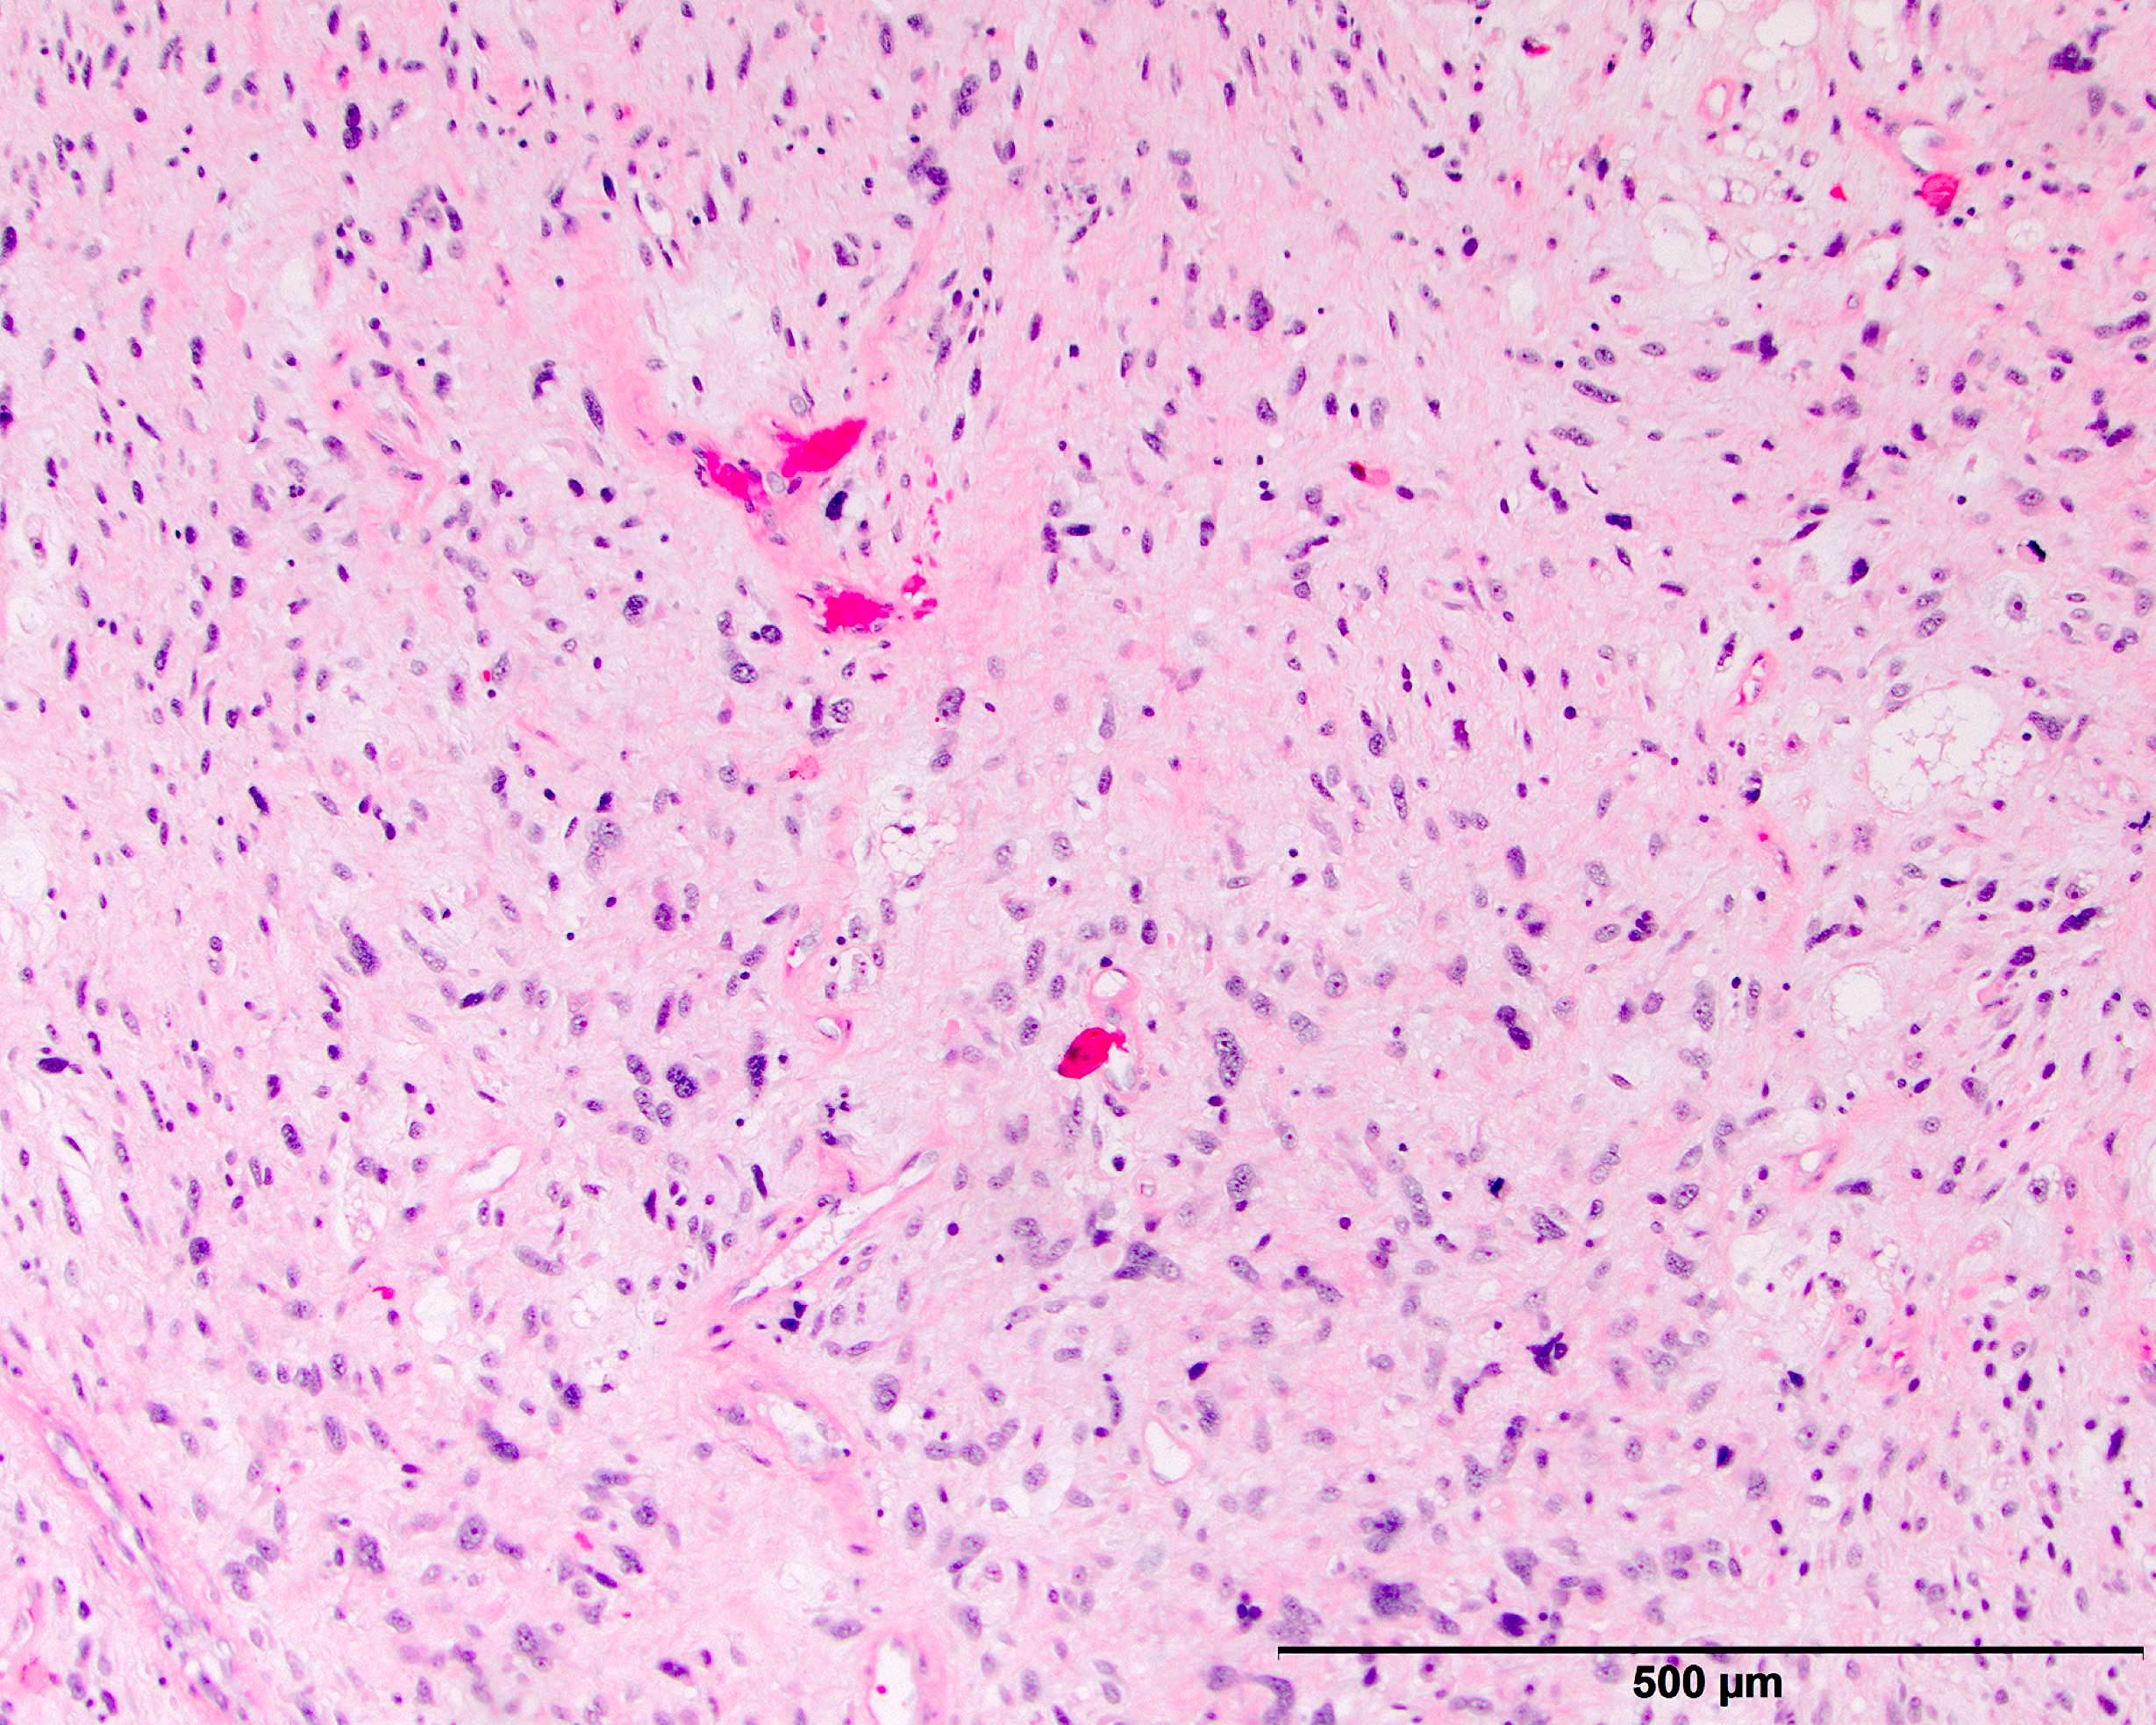

- High grade dedifferentiated liposarcoma

- Dedifferentiated component is a cellular and typically a nonlipogenic sarcoma with significant pleomorphism

- Often resembles malignant fibrous histiocytoma (MFH), now referred to as undifferentiated pleomorphic sarcoma (UPS), with short fascicles of pleomorphic spindle cells associated with mixed inflammatory infiltrate

- Heterologous elements in 5 - 10% of cases

- Can manifest as neural differentiation, leiomyosarcoma, osteosarcoma / chondrosarcoma, rhabdomyosarcoma or pleomorphic liposarcoma (homologous lipoblastic dedifferentiation)

- Dedifferentiated liposarcoma often shows a significant amount of heterogeneity (multiple patterns of differentiation and growth) and the confusing nature of the tumor can be a clue to the correct diagnosis

Microscopic (histologic) images

Contributed by Michael R. Clay, M.D. and AFIP